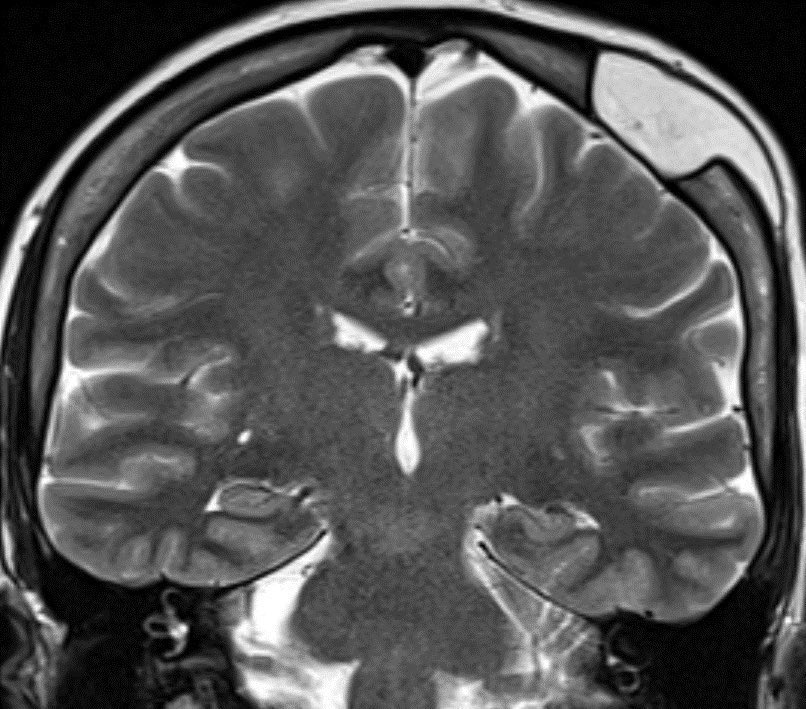

2️⃣DNET

▶️Cortically based mass in children and young adults presenting with long-standing seizures

▶️Most frequently occurs in temporal and frontal lobes

Imaging:

▶️Classically presents as a well demarcated cortically based “BUBBLY” mass with HYPERINTENSE RIM AROUND CYSTS ON FLAIR ImageImageImage

▶️Usually there is NO ENHANCEMENT (though can have punctate or ring enhancement). However, when enhancement is seen, consider the possibility of more aggressive tumors.

▶️Companion case below of another DNET ImageImageImage